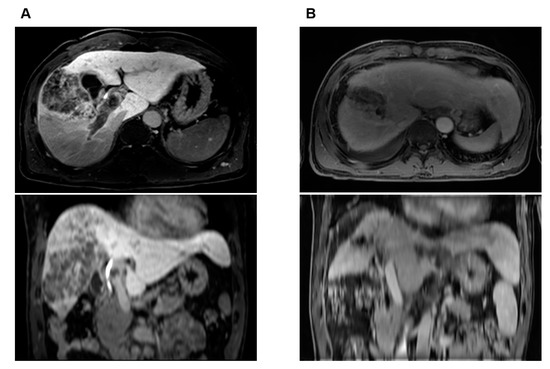

| 2 | 51/M | 15.7 | II | Bilateral | LD-CCRT | PR | 17.1 | Lt. hepatectomy | Completely necrotic tumor | 76.2 |

| 3 | 45/M | 12 | II | Bilateral | LD-CCRT | PR | 6.3 | Liver transplantation | Multiple viable HCCs, largest 2.8 × 2.8 cm, with 95% necrosis | 79.0 |

| 4 | 51/M | 8.6 | I | Bilateral | LD-CCRT | PR | 10.4 | Lt. lobectomy | 5 × 4 cm HCC, with 95% tumor necrosis | 109.6 |

| 5 | 51/M | 10.5 | III | Bilateral | LD-CCRT | CR | 5.6 | Rt. lobectomy | Completely necrotic tumor | 101.5 |